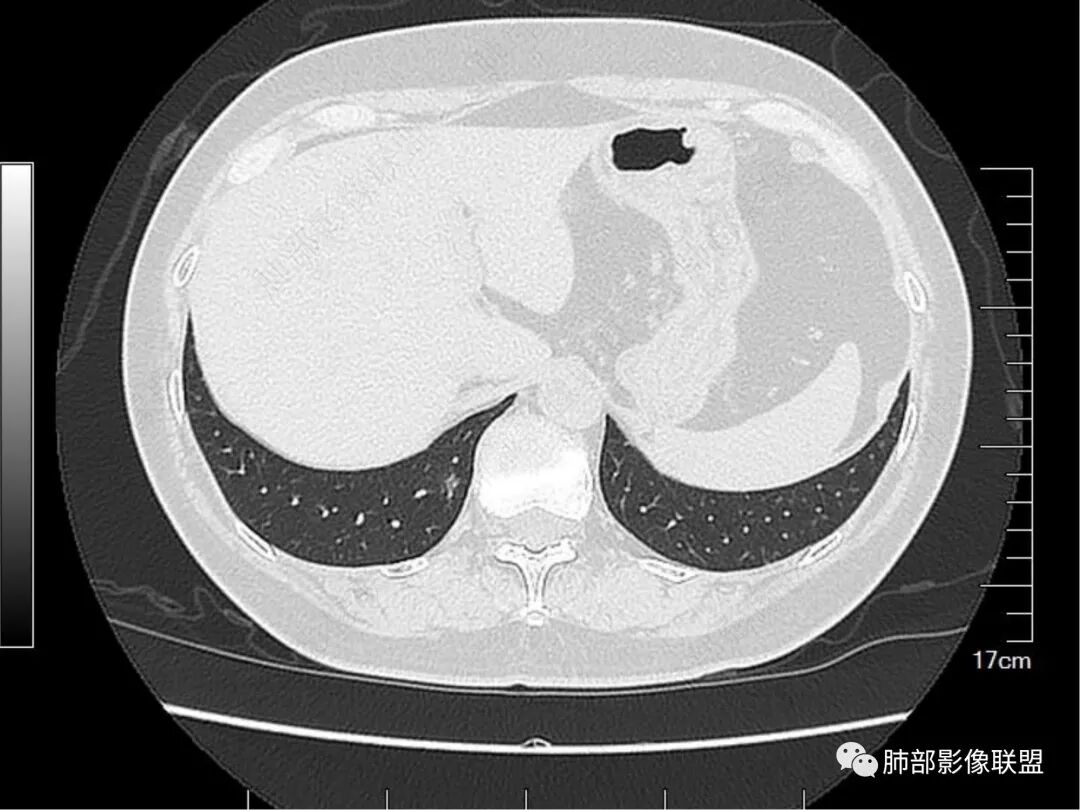

总结一下病变表现:病变区肺小叶背景不干净。整体位于单个次级肺小叶内,围绕小叶中心结构,部分局限于reid小叶的病变。支气管的显影,是肺泡填充为主要因素,收缩力可以有,但比较轻,或者无收缩力。小叶间小静脉存在增粗或者相应走行区存在局限性的淋巴道病变。

那么这个病变的疾病谱有什么呢,我们边说边鉴别。

1.细支气管畸形结节。细支气管畸形结节的本质是细支气管水平的错构,细支气管扩张明显、平滑肌增生轻,就是细支气管畸形,平滑肌增生明显,细支气管扩张偏轻,就是错构瘤。

根据我们的分析,再仔细看细支气管分支走行,还算是逐级变细的,而且分支正常。所以,不倾向于细支气管畸形结节。而且细支气管畸形结节的发病率偏低。

2.非黏液性的腺癌。假如是非黏液性的腺癌,病变已经不小了,那么密度偏高的区域就倾向于实性成分,而此时,支气管扩张是牵拉扩张,收缩力引起的,但邻近的胸膜及邻近的血管分支,明显的没有牵拉的意思。所以,用腺癌来解释,总体感觉有点矛盾。

3.黏液性腺癌。黏液性腺癌的特点是漂,发生邻近淋巴道侵袭的可能性低。小叶间小静脉的结节感,无法解释。黏液腺癌不作为首要诊断。

4.淋巴瘤。淋巴瘤的病变是位于淋巴管和淋巴组织,这个怀疑淋巴瘤的地方,就是可疑牵拉支扩、小叶间静脉走行区结节感。但是,这个结节感太局限了,仅仅局限于reid小叶的一侧隔,而且淋巴瘤解释不了次级肺小叶的不干净的背景。

5.结缔组织病相关的间质性改变。病灶比较局限,其他肺背景干净,我觉得不作为第一诊断。

6.慢性炎、非特异性感染。急性炎肯定不作为首先考虑的。慢性炎符合吗?

慢性炎的病理特征,可以有含气量较小的“肺泡塌陷”区,可以有邻近的沿着间质走形的不规则的纤维间质增生,可以解释小叶间小静脉走行区的结节感,而且是单侧的,局限性的结节感。

那么用慢性炎来解释这个结节感的时候,很明显,不是血管因素造成的。还剩下两种可能,一个是淋巴道的增生,一个是其他结缔组织成分的增多,比如纤维。

用慢性炎可以解释其他改变吗?当然可以,比如,“肺泡塌陷”区密度低,就可以是磨玻璃表现。

肺泡塌陷或肺泡填充与邻近的隔合并,就是这个细网格。

慢性炎也可以解释病变区次级肺小叶背景的不干净。

诊断综合一下:

1.慢性炎性改变、局部肺泡腔含气量少,合并周围淋巴道的反应增生或不规则的间质纤维增生。

2.肿瘤的不典型表现。放在第二位。

实际工作:一年稍增大,邻近胸膜无任何改变,可以考虑继续随访,因为病变有所增大,建议缩短随访期限,降低随访风险。